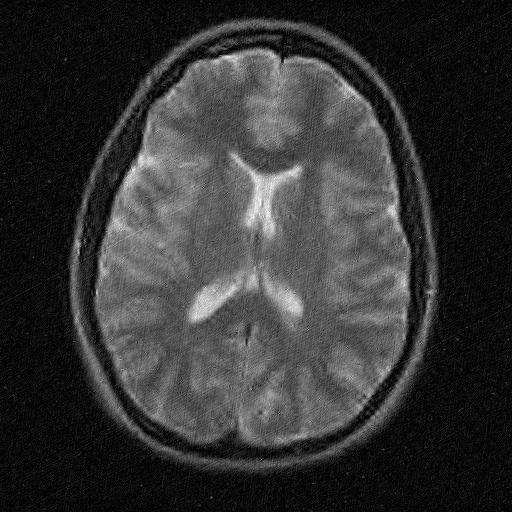

The second imaging application is concerned with medical imaging. Following the ideas from [32, 34], we simulate a multi-channel MRI sensing set-up, first using the same sine waves as in the previous experiment (results displayed in Fig 10), and then using spherical beam pattern (see in Fig. 11 for the results). We generate the classical Shep-Logan phantom, and set its dimension to .

The first experiment, depicted in Fig. 10 shows the results obtained by our method when using a Daubechies 4 sparsifying dictionary. Our results are compared to the single sensor analysis, and the results obtained by the Sum-of-Squares recovery [34, 32].

The recovery is obtained from noisy measurements, in which some additive Gaussian noise with variance has been added. The measurements are obtained by subsampling ( samples) of the Fourier transform. We see here that the fused compressed sensing is better capable of handling a multi-channel problem with unusual illumination (compared to the Sum-of-Squares method). Moreover, more details are preserved, when compared to the single sensor analysis method.

Some noise still appears in the image, but can easily be thresholded further if needed. One important aspect of MR Images that hasn’t been considered in this research, is the fact that they are sparse in gradient. One usually prefers to minimize the Total Variation instead of the norm or another frame using analysis.